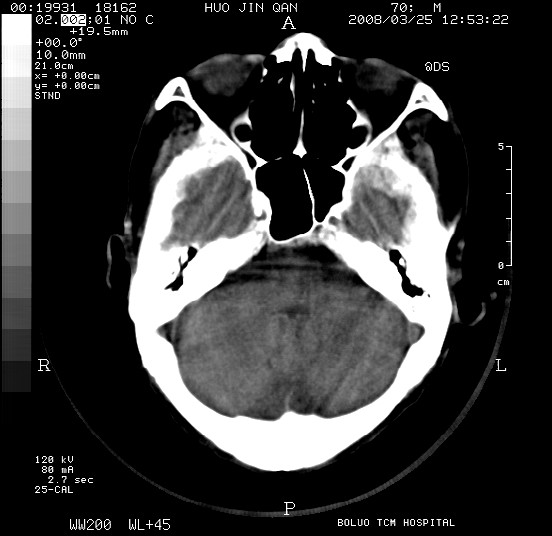

以下是引用随光逐影在2008-3-25 20:15:00的发言:[br]双侧额颞顶部亚急性(或慢性)硬膜下血肿。

以下是引用liuyue在2008-3-26 18:57:00的发言:[br]以下是引用随光逐影在2008-3-25 20:15:00的发言:[br]双侧额颞顶部亚急性(或慢性)硬膜下血肿。 [br]支持![br]可以无明显外伤病史,老年人可以在激烈摇晃或轻微头部碰创头部时,发生硬膜下出血.